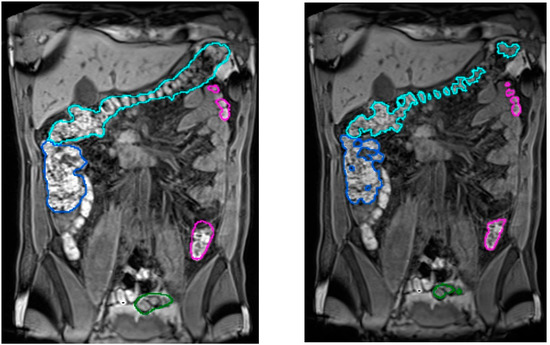

Figure 5.

Comparison of segmentation results in a T1-FS coronal slice. In the left image, the original slice visualized with the corresponding automatic colon segmentation outlined using a different color for each of its segments. In the right image, the same coronal slice is visualized with the corresponding manual identification of the fecal content, used as a ground truth in the validation process.

Regarding the validation of the colon segmentation in T1-FS images, the algorithm accuracy was evaluated by comparing the automatic segmentation results to manual segmentations of the colonic fecal content (taken as ground truth) performed by the specialist (in [15] the validation experiments were presented). Note that the specialist only segmented the fecal content because the complete segmentation was too demanding and almost impossible in areas where no fecal content was presented (areas with gas).

In total, 90 scans obtained from 35 healthy volunteers (8 women, 27 men; 20–28 Kg/m2 body mass index range) were used. The quantitative validation metric, named R, was defined as the percentage of ground truth fecal content inside the colon segmentation result. The achieved accuracy was (μR = 96.2%, σR = 4.2), demonstrating its viability for clinical usage (see Figure 5). The mean execution time was 9 min without any human intervention.